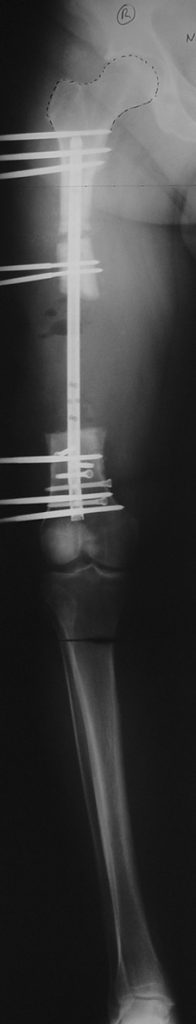

Appropriate radical debridement necessitates excision of all necrotic bone and soft tissues, and frequently causes instability at the involved extremity. The remaining bone and soft tissue defect has to be fixed and reconstructed. The distraction osteogenesis method of Ilizarov is used successfully for achievement of union, correction of the deformity, elimination of limb length inequality and reconstruction of segmental bone defects.

The duration of external fixation (external fixation index) depends on the amount of distraction required, and the extremity is prone to complications during this period. After the distraction phase is completed, the external fixator remains in place during the consolidation phase, which lasts twice as long as the distraction phase; but this period is hardly tolerated. If the external fixator is removed before sufficient consolidation is achieved, fractures, deformity and shortness will be the result. In our department, ‘lenghthening over nail’ method is used in order to decrease the external fixation index and increase patient comfort and activity level. In this method, the intramedullary nail is statically locked after the completion of the distraction phase, and external fixator is removed. The extremity is stabilized by the intramedullary nail during consolidation phase. In this way, complications due to long external fixation index or early removal of the external fixator are avoided.